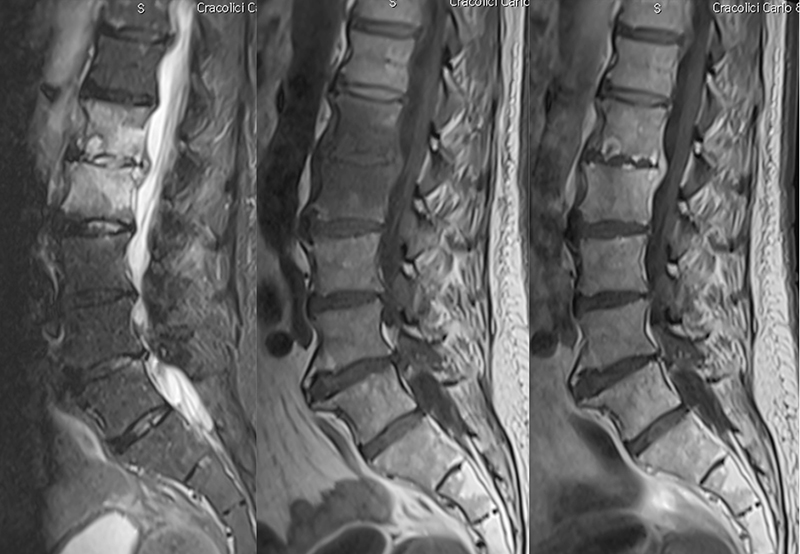

Spondylarthrite ankylosante